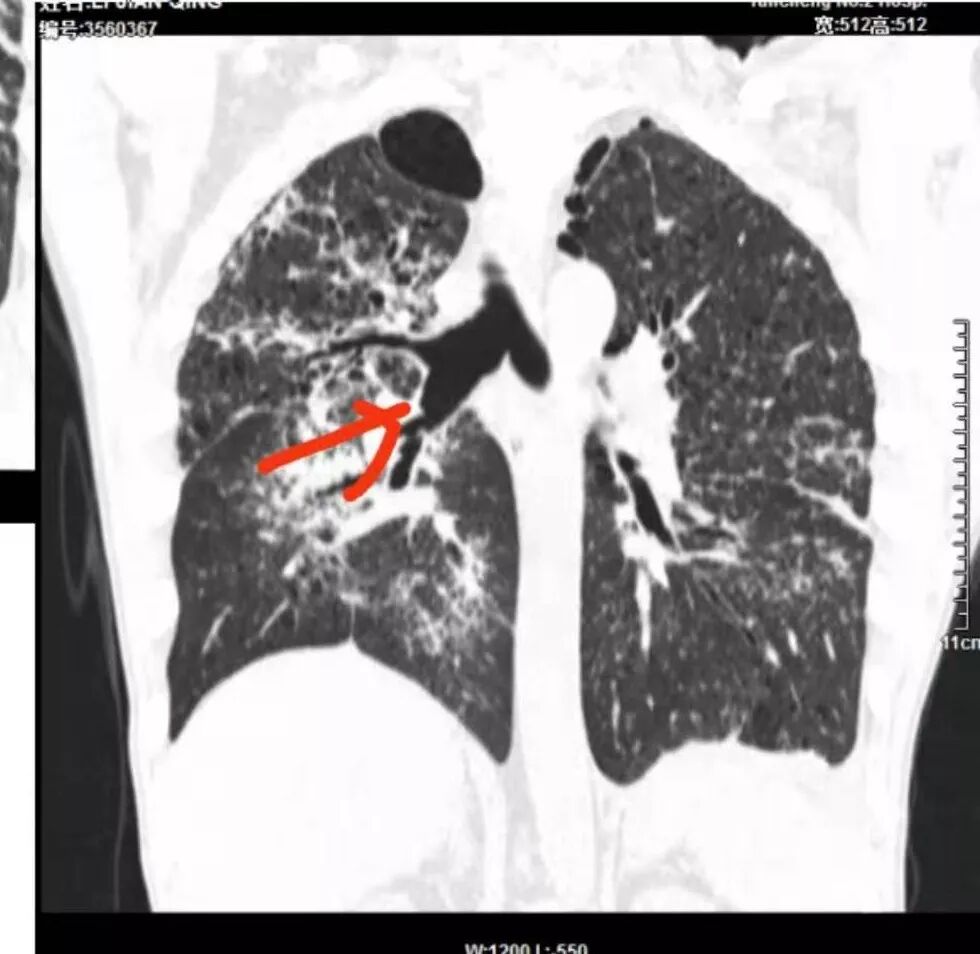

病灶呈片状磨玻璃密度影,呈典型的烟花征。磨玻璃影密度偏高,有网结节样改变,与正常肺实质分界清楚,且常见相对高密度的勾画。

烟花征分为3肿类型:晕征、反晕征及均匀分布。

病变一般沿血管支气管束分布或小叶分布,一般上肺多于下肺(这与常见继发性肺结核分布相若)。

常会伴有其他继发性肺结核病灶,如斑片影、结节影,树芽征,新旧不等改变。

2. 肺气肿背景(小叶中心性肺气肿);双肺多发病灶整体沿血管支气管束及胸膜下分布,以上叶及下叶背段分布为主,有实变及GGO,边界清楚,有树芽,小叶间隔及中央间质增厚,叶间裂见到多发结节,部分支气管不规则牵拉扩张,提示病灶纤维化明显,结合临床病史,考虑病灶为间质性感染,肺门及纵隔内有钙化淋巴结,小叶间隔结节,考虑淋巴道增值性疾病可能,综合常规要怀疑间质性肺结核。

3.  该病例临床提示感染,有支气管扩张,提示纤维化,需要与感染后的OP鉴别,但是OP病灶常无结节感;间质性肺结核有时与不典型结节病鉴别也比较困难,结节病常以双肺门淋巴结增大为特征。临床上结核发病率较高。